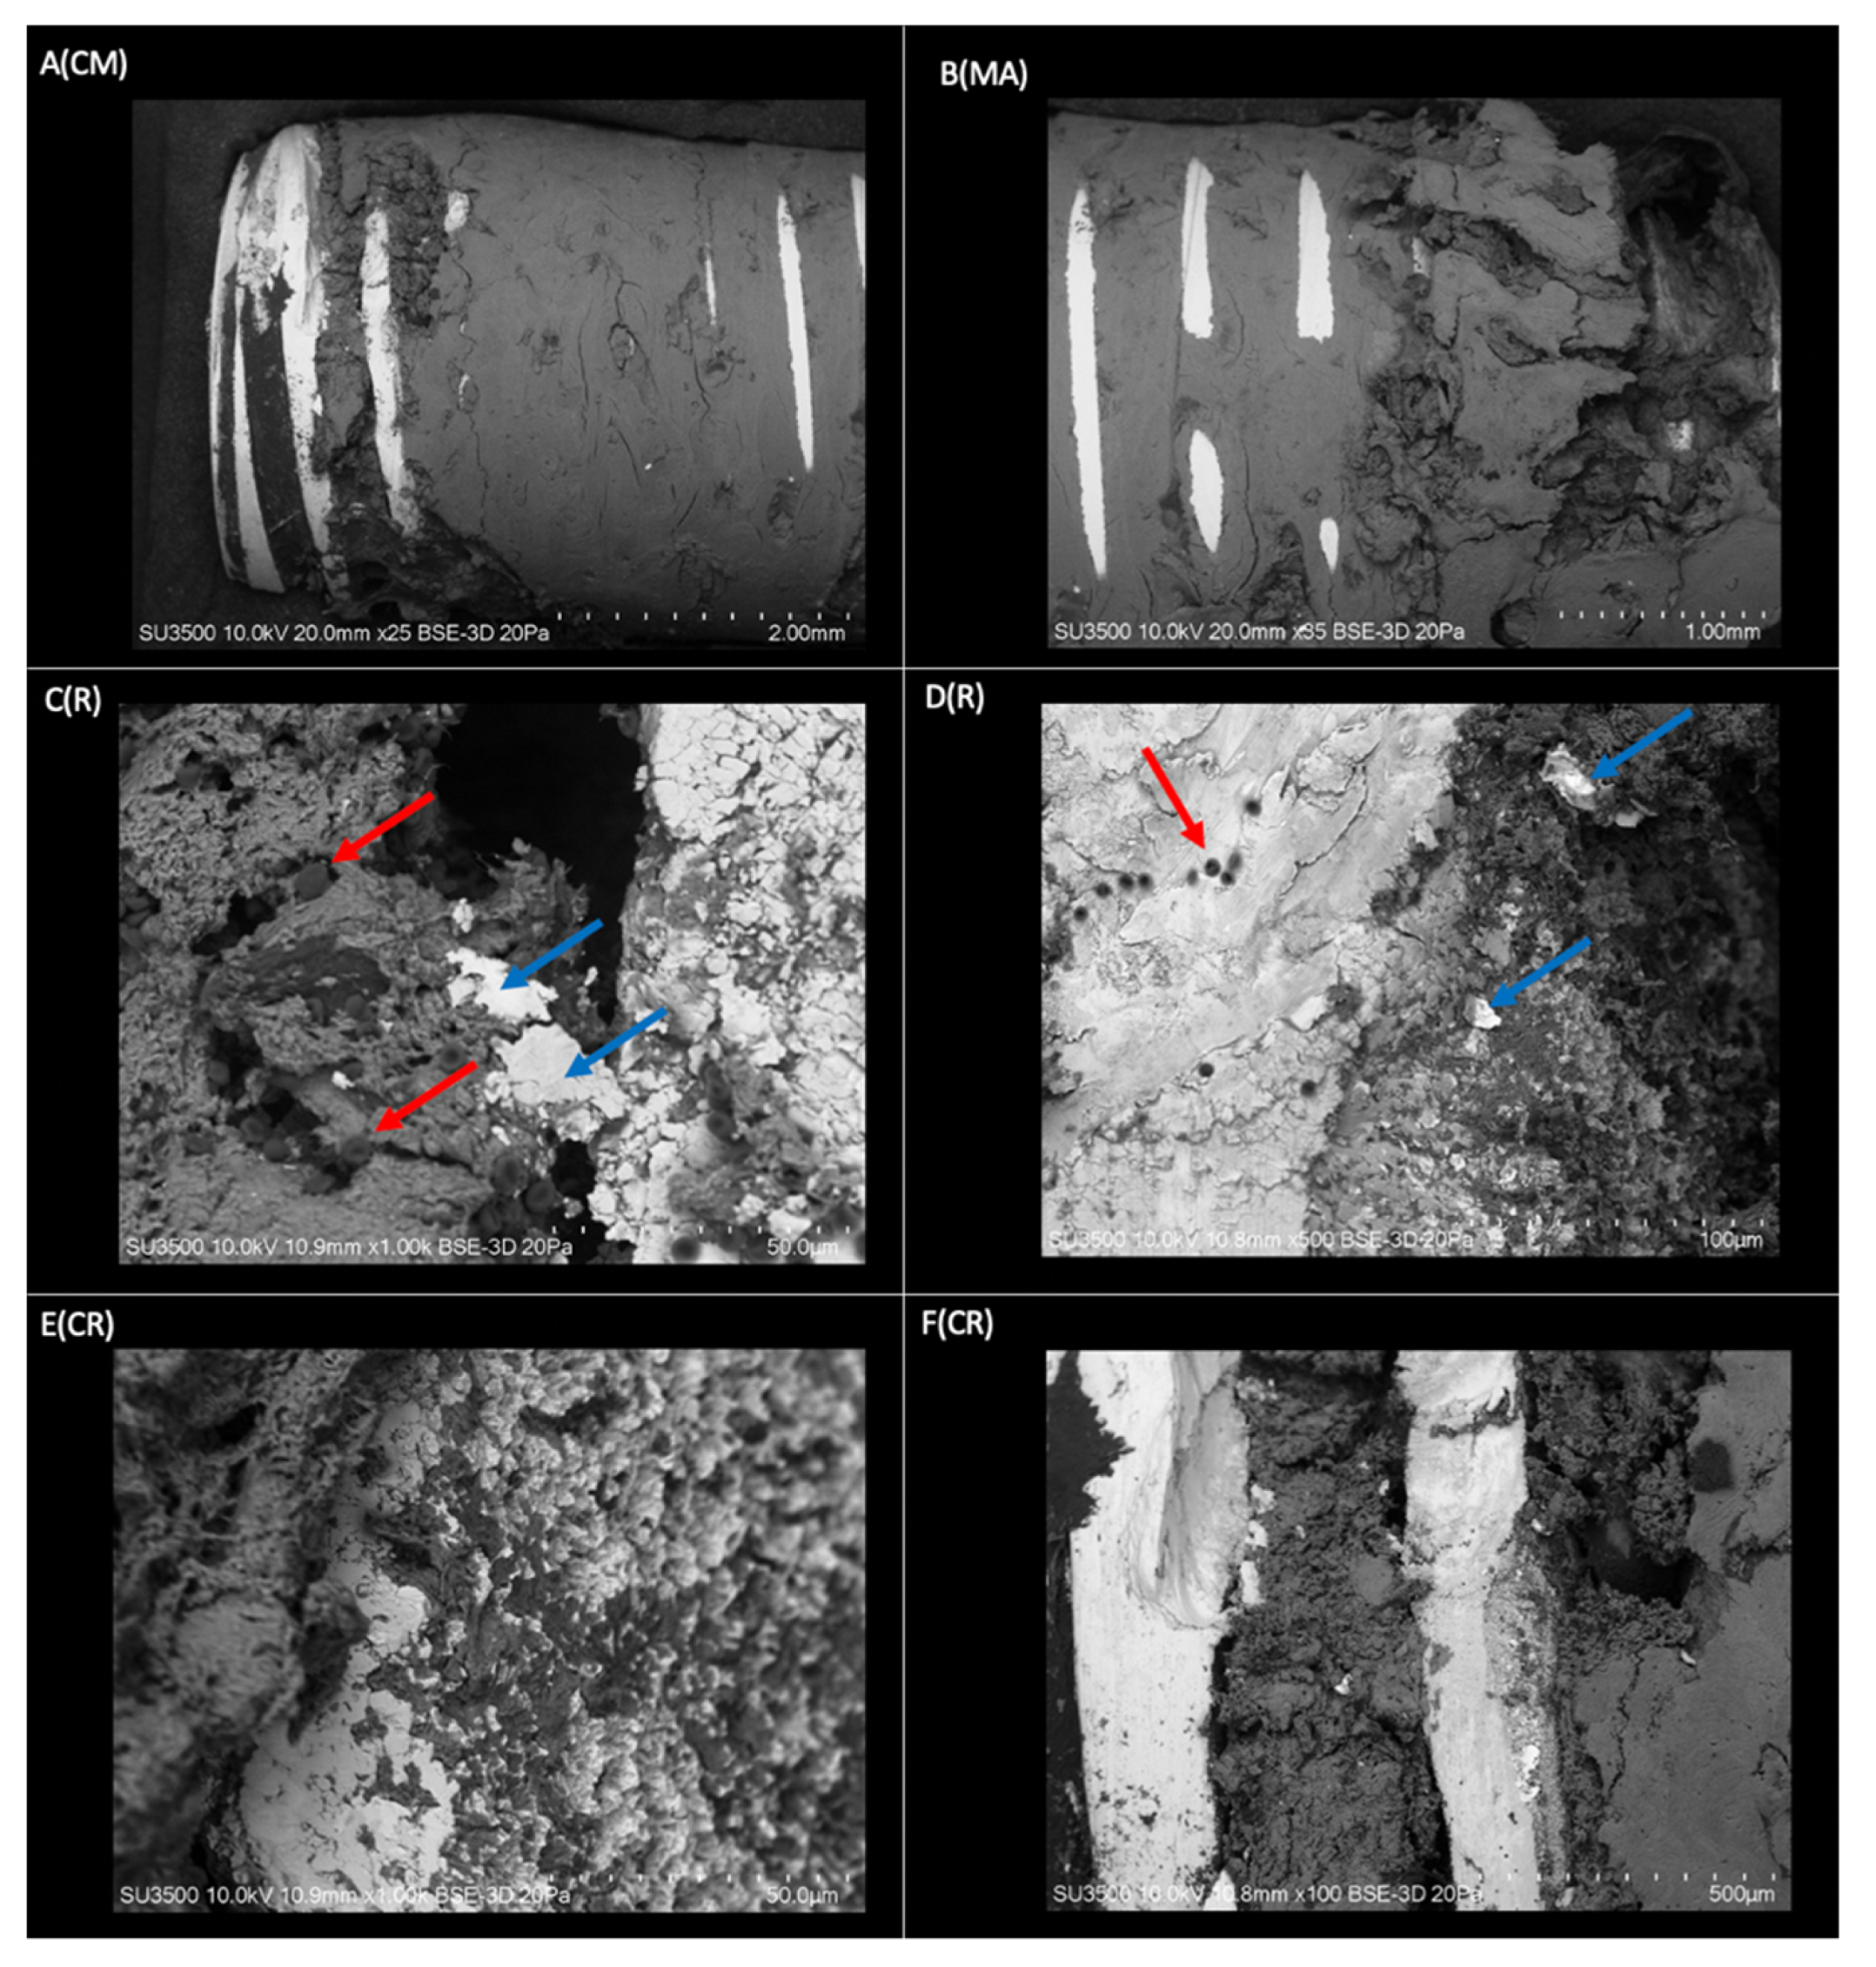

The sample of bone tissue integrated into a dental implant, processed for observation under a VP-SEM, is shown in Figure 2. The evaluation confirmed that the implant is surrounded by bone tissue integrated into the metallic surface that joins the implant threads (Figure 2A(CM),B(MA)). This confirms that practically the entire implant surface is involved in the osseointegration process, showing a very close spatial relationship between the Ti and bone tissue in the irregularities of the implant surface (Figure 2E(CR)). In a lower magnification image (Figure 2B(MA)), bone tissue can be seen crossing the areas of the metallic crests of the threads. At higher magnification (Figure 2F(CR)), the osseointegration process is again confirmed by the presence of bone tissue occupying the entire slot between the implant threads. The coronal–medial area of the implant shows a compact and homogeneous bone structure; however, in the apical zone, it is characterized by a more irregular and sinuous morphology. In the threads of the coronal area, the structure of the implant can be observed, which indicates that the space between the cell layer and the oxide is very thin, and there is bone resorption at the level of the coronal third. The presence of mineralized bone tissue interface with small groups of erythrocytes is an indicator of the maturity of the osseointegration process.

Figure 2.

Three-dimensional structure of the implant sample covered with bone tissue obtained by VP-SEM. A(CM) Coronal area-middle of the implant. The bone tissue homogeneously covers most of the implant. Smooth surface in conformation to bone laminar zones (Mag: ×25). B(MA) Mid-apical area of the dental implant. Morphologically rougher and more sinuous tissue in the apical sector compared to the middle zone (Mag: ×35). C(R) Thread on the right side of the image and groove on the left side of the image, covered by mineralized and non-mineralized cancellous bone tissue with associated red blood cells (red arrows) and flaking of the implant surface (blue arrow) (Mag: ×1000). D(R) Implant thread (light grey) with fully associated bone tissue (dark grey) and presence of red blood cells (red arrow). Spalling of the dental implant surface (blue arrow) (Mag: ×500). E(CR) View of an implant thread at higher magnification (light gray area). Integration of bone tissue (dark gray area) in the irregularities on the implant surface (Mag: ×1000). F(CR) Implant threads without bone tissue and grooves completely covered by bone tissue (Mag: ×100).